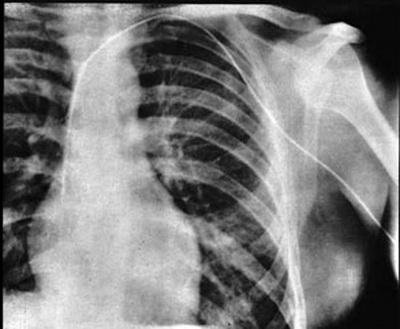

Пока медики спорили, он под анестезией ввел себе в вену на руке катетер длиной 60 см и вошел в сердечную мышцу. Затем ему сделали рентген, чтобы доказать, что катетер в сердце.

Главврач все равно был против, но со временем отношение к этому методу изменилось.